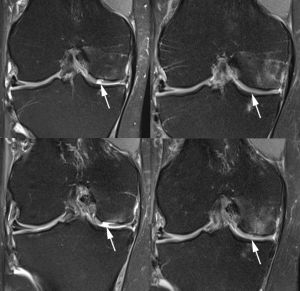

Συνήθως οι ασθενείς φτάνουν στον γιατρό με βλάβες σταδίου 3 και 4, που επηρεάζουν τη φυσιολογική λειτουργία της άρθρωσης και προκαλούν πόνο, ύδαρθρο και θορύβους κατά την κίνηση. Το πιο πιθανό είναι να ανήκουν στον αθλούμενο πληθυσμό και να είναι νεαρής ηλικίας – αιτία μπορεί να είναι ένας συγκεκριμένος ή και επαναλαμβανόμενος τραυματισμός, είτε η οστεοχονδρίτιδα.

Οι χόνδρινες βλάβες δεν αντιμετωπίζονται συντηρητικά. Η χειρουργική αποκατάστασή τους γίνεται κατά κύριο λόγο με αρθροσκοπικές τεχνικές και μόνο σε περιπτώσεις εκτεταμένης βλάβης χρησιμοποιούνται ανοιχτές τεχνικές. Ειδικά σε επαγγελματίες αθλητές είναι δυνατό να γίνει αρθροσκοπικά αφαίρεση ενός ελεύθερου χόνδρινου σωματιδίου που «ενοχλεί» την άρθρωση, και η τελική χειρουργική αποκατάσταση της βλάβης να πραγματοποιηθεί σε δεύτερο χρόνο.

Για βλάβες που καταλαμβάνουν μικρή επιφάνεια του χόνδρου επιλέγονται οι τεχνικές των μικροκαταγμάτων και των μικροτρυπανισμών ώστε να ανοιχτούν δίαυλοι «επικοινωνίας» μεταξύ του τραυματισμένου χόνδρου και του υποχόνδριου οστούν που είναι πλούσιο σε μεσεγχυματικά κύτταρα, τα οποία μετασχηματίζονται σε χονδροκύτταρα όταν τοποθετηθούν στις προβληματικές επιφάνειες. Βέβαια ο νέος χόνδρινος ιστός που σχηματίζεται είναι κατώτερης ποιότητας και περιορισμένης μηχανικής αντοχής.

Εναλλακτικά εμφυτεύονται οστεοχόνδρινα κυλινδρικά τεμάχια που προέρχονται από περιοχές της πάσχουσας άρθρωσης και δεν συμμετέχουν στη λειτουργία της, ή συνθετικά μοσχεύματα. Το πλεονέκτημα αυτής της τεχνικής είναι ότι τοποθετείται έτοιμος χόνδρος, και έτσι αντιμετωπίζεται και τυχόν συνυπάρχουσα βλάβη του υποχόνδριου οστού (οστεονέκρωση). Το ποσοστό επιτυχίας φτάνει το 80-90%, ωστόσο μειονέκτημα θεωρείται ο περιορισμός στο πόσοι κύλινδροι μπορούν να ληφθούν από τη δότρια περιοχή.